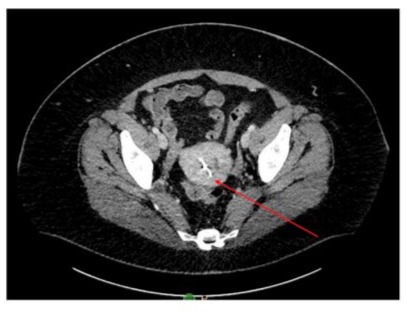

The patient then sought consultation for a re-attempt at surgical removal. Prior to the procedure, a CT pelvis was performed to assess the distance of the IUD from the serosa and the uterine cavity to determine the appropriate surgical approach. The CT scan, chosen over MRI based on the radiologist’s recommendation, confirmed the presence of the IUD within the uterus but reported it as normally placed in the cavity, despite direct visualization suggesting otherwise. The patient was subsequently consented for both hysteroscopic and potentially robotic retrieval of the embedded IUD.

Figure 1: CT imaging showing the IUD within the uterine cavity (indicated by the red arrow).